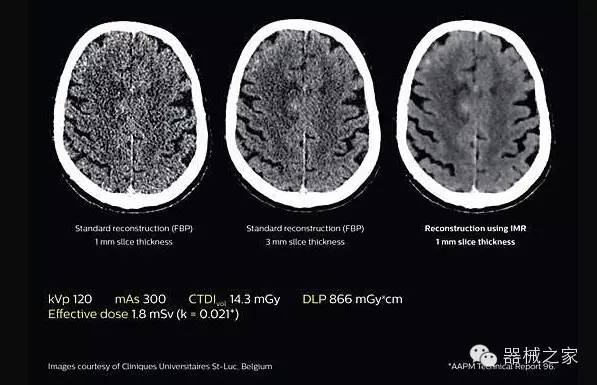

2.腦部顯影

透過數(shù)字化影真芯片DAS系統(tǒng)、球面微平板探測器技術(shù)和濾線柵技術(shù)等硬件技術(shù),整體提高探測器成像的能力,奠定低劑量條件下高清成像的基礎(chǔ);

應(yīng)用目前業(yè)界領(lǐng)先的新一代星光平臺iDose4 Premium及基于迭代基礎(chǔ)的O一MAR去除金屬偽影技術(shù),達(dá)成微量輻射下零偽影的高清晰成像;